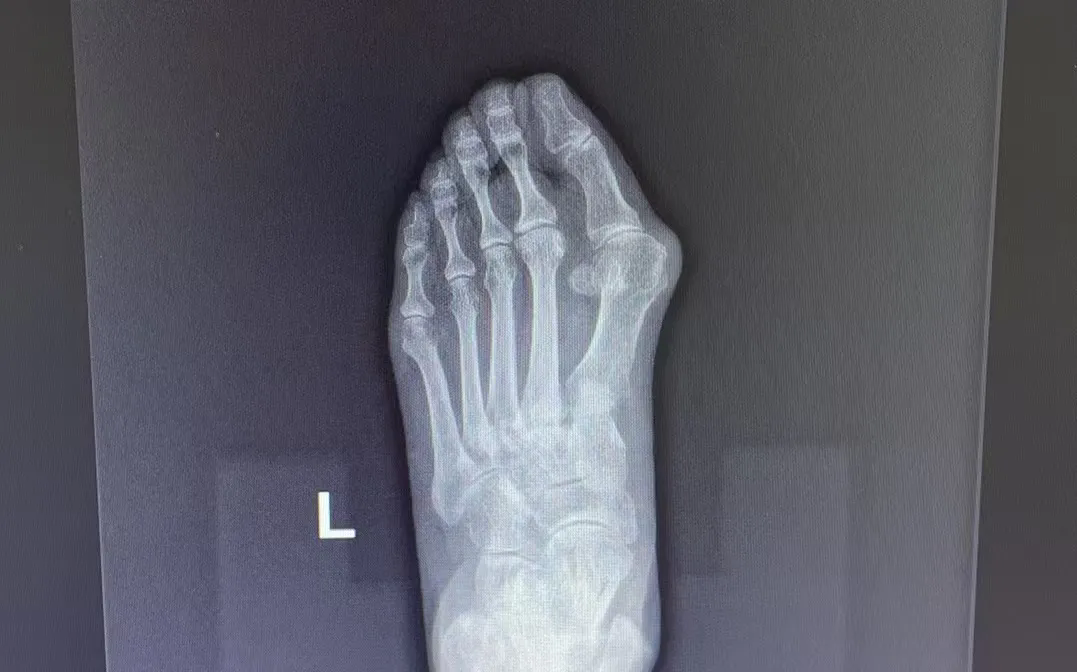

拇指外翻

這一復(fù)雜的解剖畸形

不僅影響美觀

更會(huì)帶來紅腫疼痛、關(guān)節(jié)炎等癥狀

拇指外翻的成因

?長(zhǎng)期穿著高跟鞋或前頭過窄的鞋子,會(huì)加劇足部壓力,導(dǎo)致拇趾外翻畸形。

?風(fēng)濕性疾病也可能引發(fā)足部關(guān)節(jié)的炎癥,進(jìn)一步加重拇指外翻的癥狀。